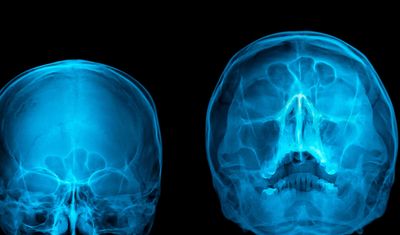

FESS - functional endoscopic sinus surgery

There are a lot of air cells which come together during development of the baby in the womb and align

themselves so that they stay in the path of airflow through the nose, within the facial bones. These cells

collectively form the sinuses which help in 1. Lightening the weight of the skull and 2. Moistening the air

we breathe by producing mucus, so it reaches the lungs without being too dry. When there is a common

cold, it typically involves swelling of the skin lining of the nose and these sinuses, sometimes this

swelling doesn’t reduce and the sinuses continue to produce mucus which cannot come out into the

airway causing stagnation. This leads to heaviness of the face, fever, headache or facial pains and when it

gets infected, we use the term sinusitis.

Prior to surgery, a CT scan is done. This acts as a guide to locate the position of infected cells, and as a

roadmap to our approach during FESS.